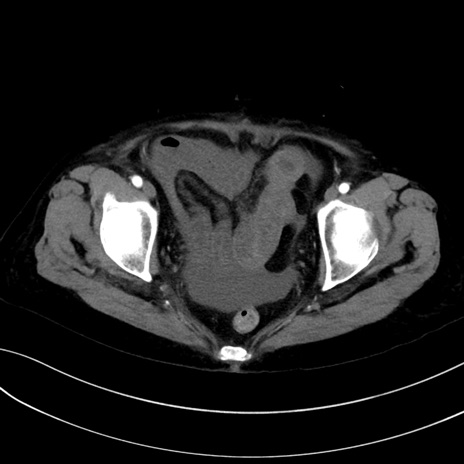

(冠状断像)1日半後